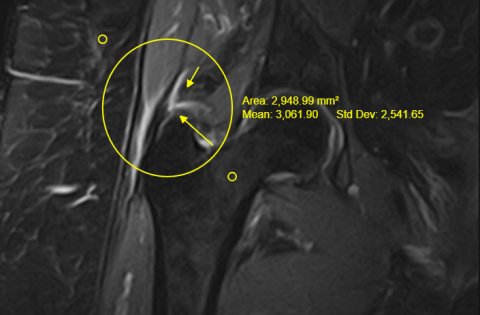

Rotura de tendons glutis en trocanteritis crònica

Pacient amb dolor de maluc D de 3 anys d'evolució sense signes d'artrosi que consulta per dolor persistent malgrat la fisioteràpia i infiltracions realitzades.

Aporta una radiologia convencional i una ecografia amb el diagnòstic de trocanteritis sense signes d'artrosi de maluc a nivell radiogràfic.